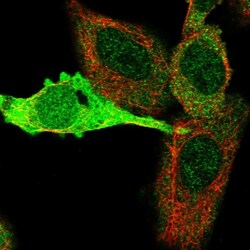

| Immunohistochemistry (Paraffin), Western Blot, Immunocytochemistry | |